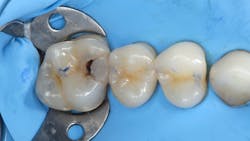

After removing a two-week-old provisional, it’s a rare day that we don’t experience some minor inflammation of the soft tissues. Even with the best prototypes/provisionals and meticulous oral hygiene, gingival tissues will bleed, exude fluids, and generally cause problems when isolating teeth for adhesive delivery. With a direct composite, the existing decay is an irritant, and the best isolation device will not address the bleeding tissue adjacent to an extensive class II cavity.

With an inverted rubber dam, however, bleeding becomes a nonissue and allows the clinician to focus on preparation design, pulpal protection, adhesive strategies, and restoration placement—all in a clean and well-sealed environment.3 “Beating the blood” need not be your approach when one of dentistry’s least-used gems is close at hand (figures 6 and 7).